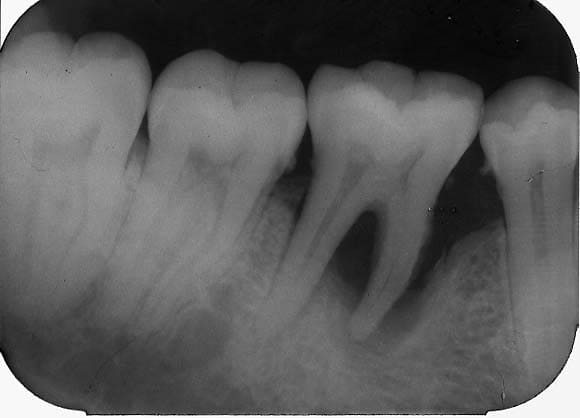

Seule la 16 est touchée. Cette fonte alvéolaire peut elle être due au phénomène diasthème-bourrage-carie distale + gingivite = parodontite ?

traitement, pronostic ?

- traitement antiseptie plus litho progressivement + controle de l'occlusion . Le probleme pour cette dent est qu'il y a sans doute une atteinte inter radiculaire avec une anomalie . Je ne suis pas persuadé aux vues de la rx que tu puisses stabiliser sur le long terme cette dent ( les atteintes IR dans ce cas......). Attention le sinus n'est pas loin. Ne prend pas trop le risque de perdre d'avantage d'os pour compliquer ensuite ton approche si tu veux mettre un implant ( si la 16 n'est pas récupérable tu fais quoi )

Il me semble entrevoir une début de zone radioclaire masquée par la radioopacité de la dent en forme semi circulaire qui se termine en distal ce qui laisse supposer une destruction osseuse beaucoup plus importante que la radio le laisse entrevoir(c'est importer d'essayer de deviner ce que la radio nous cache; importante lyse osseuse palatine ou vestibulaire). d'autre part la conicité radiculaire est un facteur hyperdéfavorable.